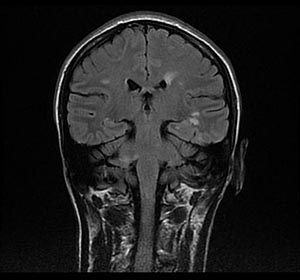

В отделение неврологии поступила 33-летняя пациента с жалобами на шаткость при ходьбе, онемение нижних конечностей, нарушение функции тазовых органов При сборе анамнеза установлено, что с октября 2009 г после перенесенной около месяца назад респираторной вирусной инфекции, сопровождавшееся катаральными проявлениями, лихорадкой, стала отмечать онемение в нижних конечностях, которое частично регрессировало в течение последующих нескольких недель без лечения. С декабря 2009 г стала отмечать появление нарушения контроля функции тазовых органов, онемение в области живота. Данные нарушения постепенно прогрессировали, что заставило обратиться в медицинское учреждение. При обследовании проведено МРТ головного мозга, не выявившее патологии. Специфическое лечение не назначалось. В начале января 2010 г к вышеуказанным проявлениям внезапно присоединилась выраженная шаткость и неустойчивость при ходьбе, скованность в ногах. Резко снизилась трудоспособность, больная был ограничена в передвижении по квартире, в связи с чем с направительным диагнозом нарушение мозгового кровообращения госпитализирована. При поступлении в отделение в неврологическом статусе: выявлялся мелкоамплитудный нистагм в горизонтальной и вертикальной плоскости с ротаторным компонентом. Имело место оживление сухожильных рефлексов с наличием патологических стопных рефлексов (симптом Бабинского с двух сторон). Брюшные рефлексы отсутствовали. Отмечена выраженная неустойчивость при ходьбе, значительные нарушения при выполнении координаторных проб, с наличием интенционного тремора. Чувствительные нарушения представлены гипестезией по проводниковому типу с уровня Th10, а также имело место нарушение функций тазовых органов по центральному типу Учитывая возраст пациентки, отсутствие факторов риска развития сосудистых осложнений, данные анамнеза о факте перенесенного вирусного заболевания накануне развития клинических проявлений, было высказано предположение, которое не позволяло заподозрить демиелинизирующее заболевание центральной нервной системы. Для подтверждения диагноза проведено МРТ головного мозга:

Картина множественных очаговых изменений вещества головного мозга (очаги расположены перивентрикулярно, паракаллезно, в области ствола головного мозга) размерами от 3 до 12 мм демиелинизирующего характера с признаками накопления контрастного вещества 6 очагами Таким образом, учитывая данные анамнеза, клинической картина, картины МРТ головного мозга с применением внутривенного контрастирования выставлен диагноз: острый рассеянный энцефаломиелит, что потребовало назначение курса пульс-терапии Солумедролом по схеме: 1000 мг внутривенно капельно в течение 5 дней. На фоне проводимого лечения отмечена значительная положительная динамика: В течение первых двух дней отмечено пациентка отмечает уменьшение шаткости при ходьбе, в неврологическом статусе регрессировали явления нистагма, признаки чувствительных нарушений. В течение последующих 4 дней имело место снижение общего рефлекторного фона сухожильных рефлексов, появление брюшных рефлексов и отсутствие патологических стопных рефлексов при клиническом осмотре. Пациентка без затруднений выполняла координаторные пробы, чувствительные нарушения выражены не были, а также отмечено восстановление контроля функций тазовых органов. Таким образом, восстановлена трудоспособность, пациентка вернулась к активной физической и умственной деятельности. По завершении курса лечения в стационаре была выписана под наблюдение невролога поликлиники по месту жительства.